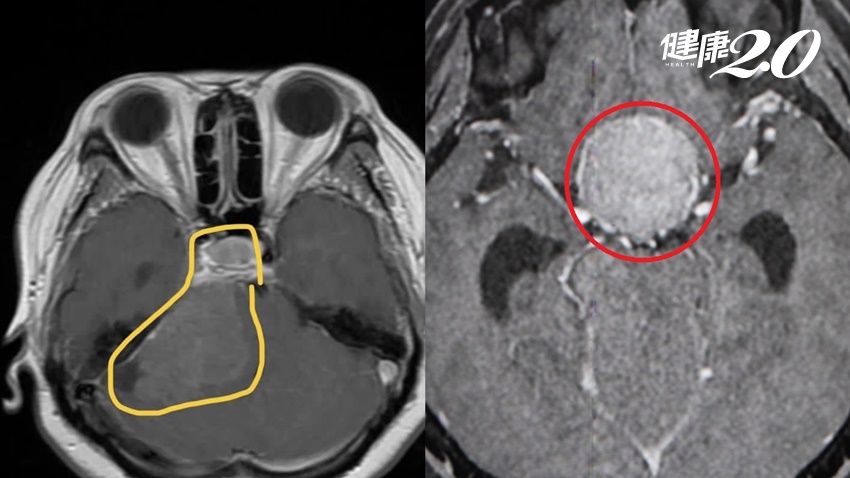

▲核磁共振檢查可見到圖左是小腦橋腦角腫瘤,圖右則是蝶鞍上腫瘤。

收治患者的長安醫院神經醫學中心副院長李漢忠表示,原先電腦斷層檢查發現病人有水腦症,所以才會出現反應遲鈍、走路不穩、小便失禁等類似老人痴呆症狀,但奇特的是病人不只視力變差,兩邊視野看的更不清楚,又有右手、右腳無力狀況,故安排核磁共振,發現除「水腦症」外,在腦部深處有7公分大的「小腦橋腦角腫瘤」合併腦幹壓迫,和3公分大的「蝶鞍上腫瘤」壓迫到視神經,而水腦症正是腫瘤因腫塊效應導致腦室阻塞,這是非常罕見又嚴重的病灶。